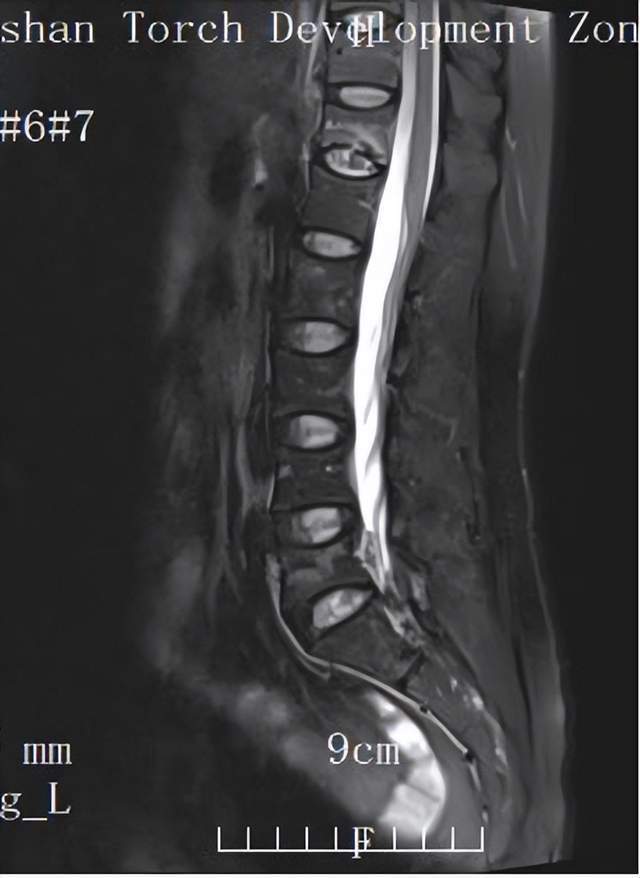

检查结果显示,患者胸12、腰5椎体发生压缩性骨折,骨骼脆弱程度远超预期。

影像学复查显示:椎体形态稳定,骨折线消失